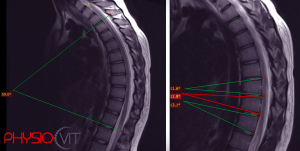

Egy szép napon, a reumatológus röntgenképet készít, és hoppá, ott virít a Scheuermann-betegség jele! Az egyenetlen zárólemezek, Schmorl-sérvek és ékcsigolyák mind árulkodóak. Azonban nem mindenkinél fedezik fel időben. Sokszor csak felnőttkorban, gerincfájdalmak miatt készült röntgenfelvételeken derül ki, hogy valakinek gyermekként Scheuermann-betegsége volt.

De miért alakul ez ki? A probléma a csigolyák és a porckorongok közötti zárólemezeknél jelenik meg. Ezek az egyenetlen zárólemezek lehetővé teszik, hogy a porckorong egy része benyomuljon közéjük, amit Schmorl-sérvnek nevezünk. Ez az ék alakú csigolya aztán a gerinc természetes görbületeit is befolyásolja, máskor pedig a görbületek laposabbá válását eredményezheti.